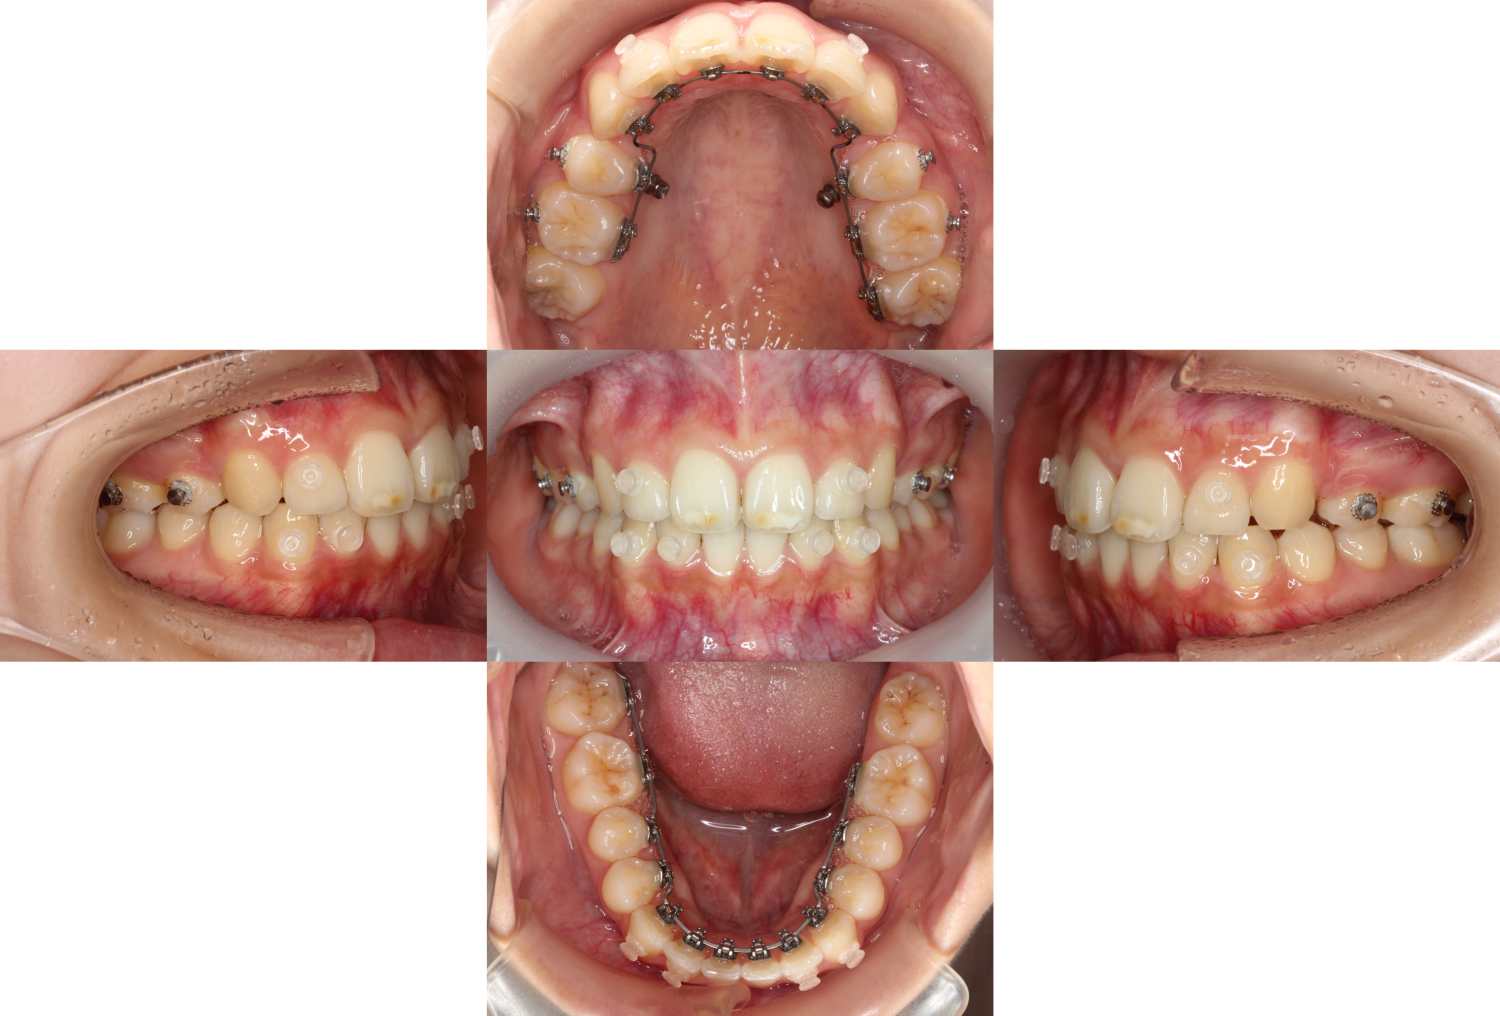

アンカースクリューを使用し、前歯を後ろに下げました。

また、表側にクリア色のボタンを装着し、

ご自身でゴムを掛けて嚙み合わせをより緊密にしていきます。

治療では患者様のご協力も必要不可欠です。